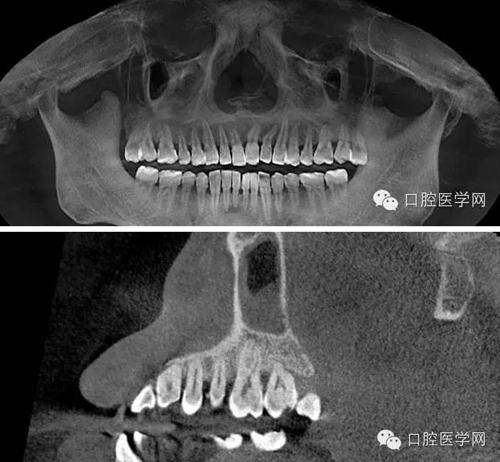

處置:必蘭局部麻醉后,于有出血點(diǎn)的牙齦乳頭處行縫合術(shù),縫合后出血明顯減少,組織同事會(huì)診,同樣口內(nèi)無明顯臨床表現(xiàn),拍攝CBCT,CT顯示26根尖可見低密度透射暗影,35、36、37無異常,為進(jìn)一步確診,遂與患者溝通采用麻醉排除法確認(rèn)患牙。26必蘭麻頰腭側(cè)浸潤麻醉,待麻藥起效后,患者告知牙齒疼痛停止,觀察五分鐘無其他異常,遂確認(rèn)患牙,建議患者行根管治療術(shù)。交代治療過程,治療風(fēng)險(xiǎn),簽署治療同意書。

CBCT截圖:26根尖可見低密度透射暗影: